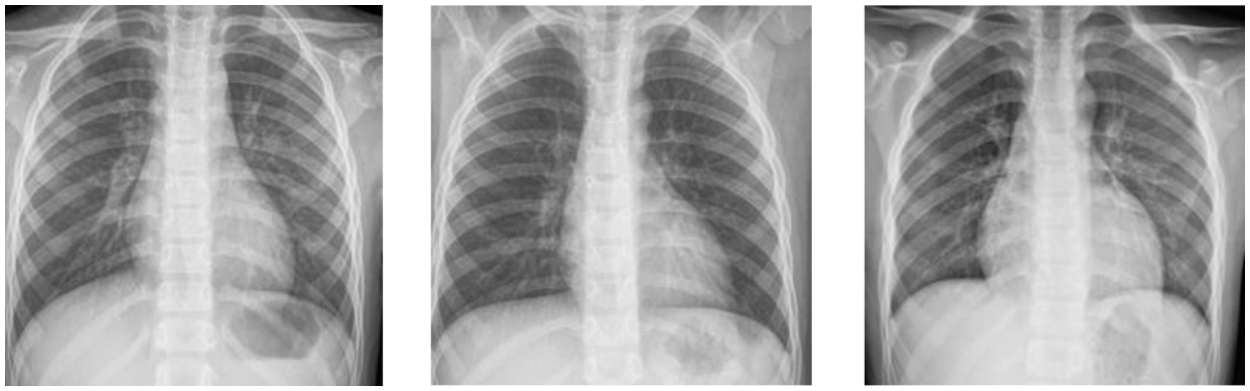

With the rapid development of Deep Learning (DL), the DL-assisted pneumonia diagnosis has been widely researched [5]. As one of the most powerful kinds of DL, Convolutional Neural Network (CNN) can handle the raw images directly and extract the feature of images for further diagnosis [6,7], and it has been widely used in the field of medical image [8]. As shown in Fig. 1, there is very little difference between abnormal sample 1 and normal sample 1, and the difference between normal sample 1 and normal sample 2 is very obvious, which is consistent with the fine-grained characteristics with small differences between classes and large intra-class differences. Therefore, it can be determined that chest X-ray images of children with pneumonia have typically fine-grained characteristics. There is little difference in chest X-ray images between normal people and patients with pneumonia, and the chest X-ray images of patients with pneumonia are diverse [4], which leads to inefficient and unreliable diagnosis methods based on CNN. Therefore, it is of great significance to develop more powerful diagnostic methods to improve the performance of CNNs on children’s chest X-ray images.

Figure 1: Children chest X-ray images, from left to right, are abnormal sample 1, normal sample 1, and normal sample 2